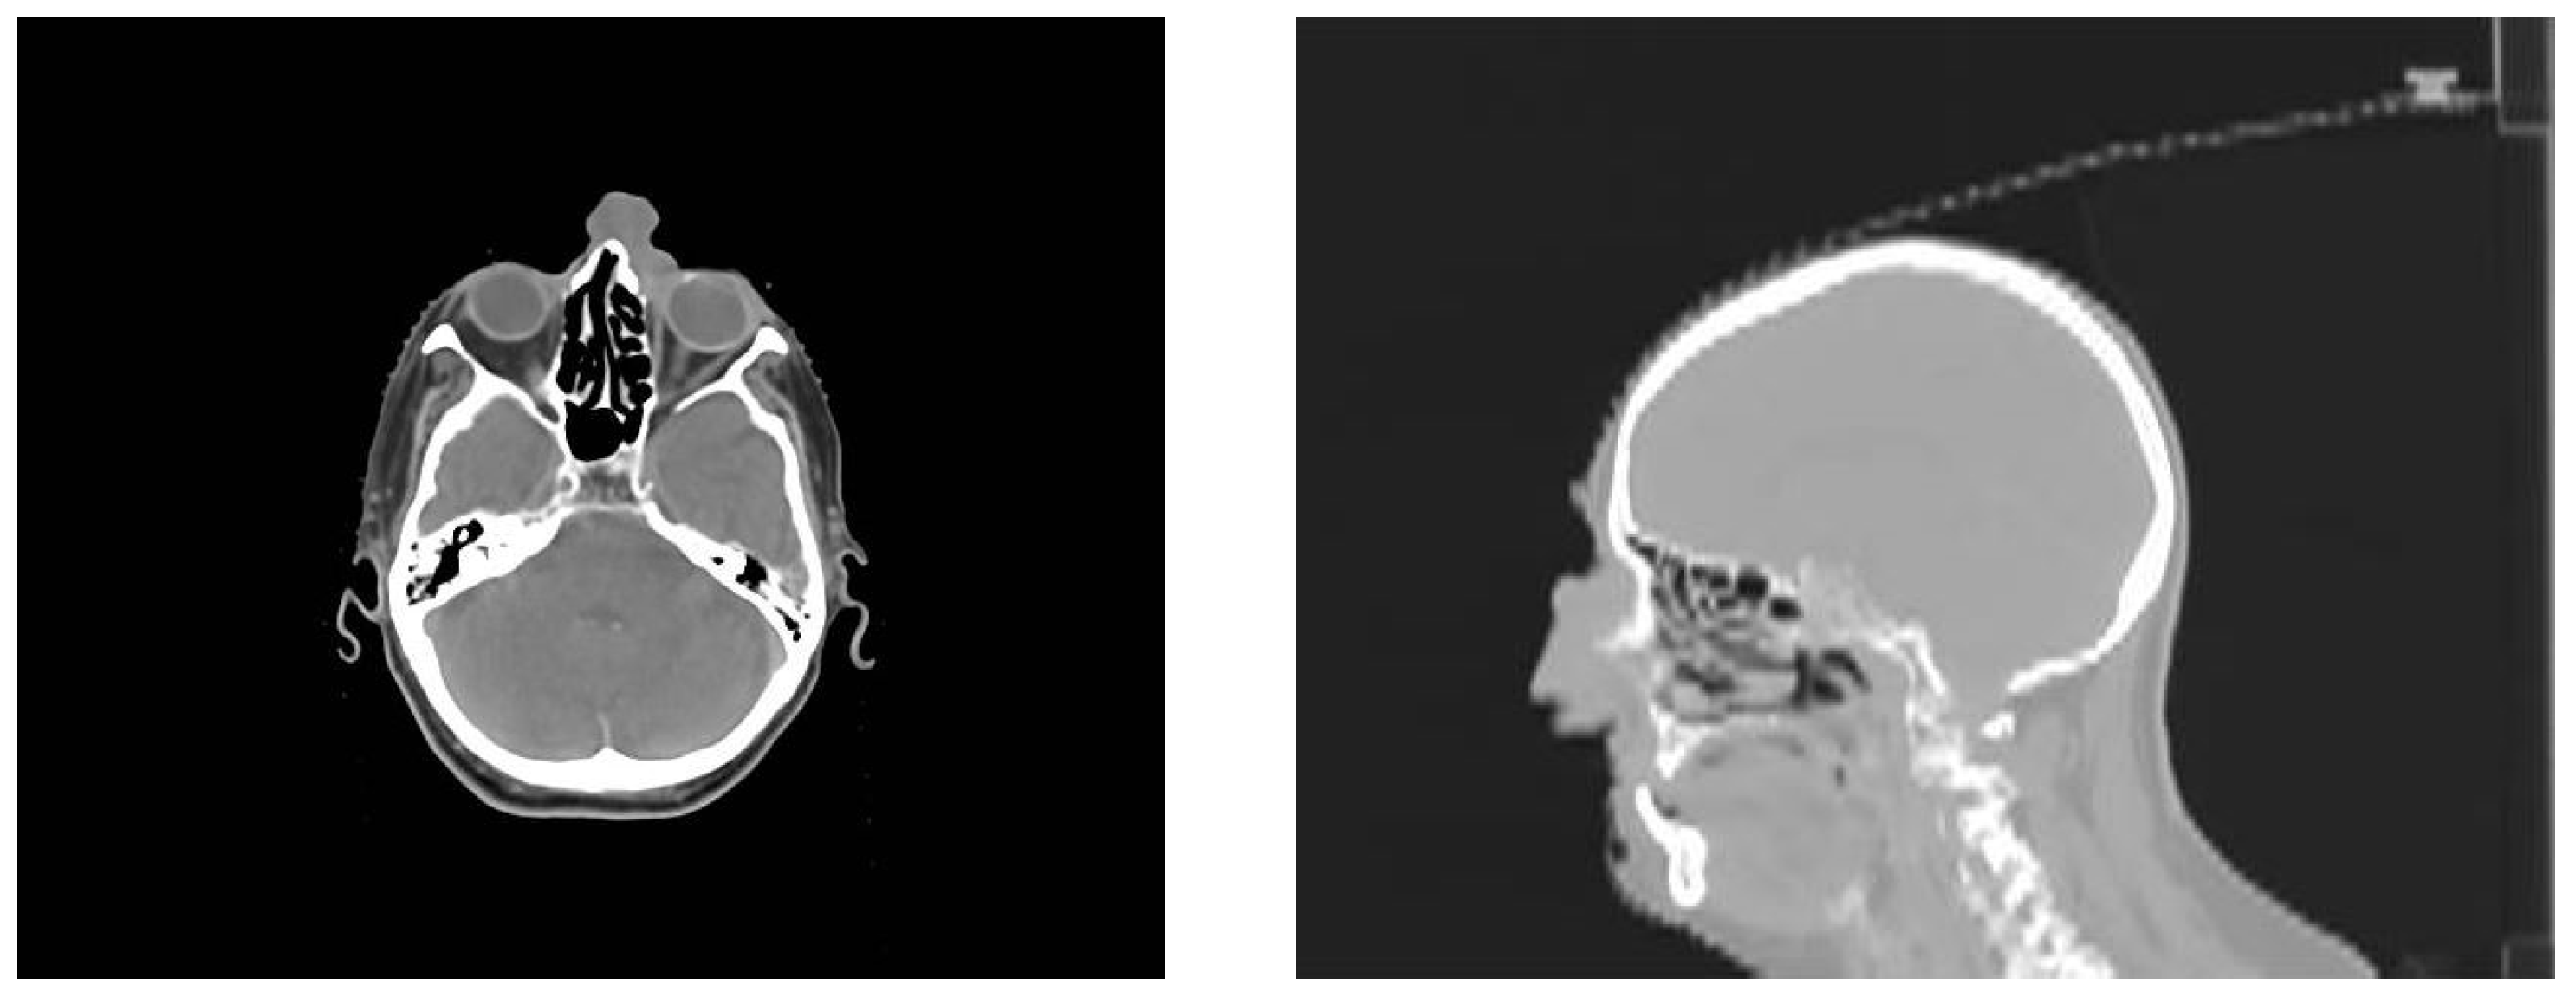

2. Presentation of the Case